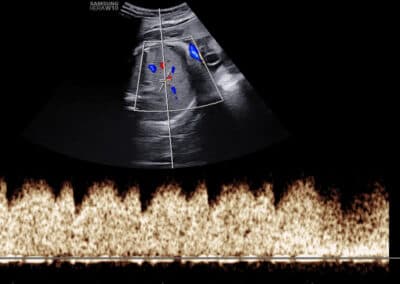

Dopplerovské vyšetření průtoku krve v pupečníkové tepně (arteria umbilicalis)

Co je to Dopplerovské vyšetření? Dopplerovské vyšetření je speciální typ ultrazvukového vyšetření, který se používá především k zobrazení průtoku krve, a to buď prostřednictvím barvy (tzv. barevné mapování) nebo křivky (tzv. pulzní vlna). Komu se doporučuje provedení Dopplerovského vyšetření krevního oběhu plodu a placenty? Toto vyšetření je velmi důležité u všech těhotenství, kde je zjištěno větší zpomalení růstu miminka. Pokud je totiž hmotnost miminka menší, než je v daném stáří miminka očekáváno, jen Dopplerovské vyšetření pomůže rozlišit, zda se jedná pouze o konstitučně menší miminko (obvykle v souvislosti s menší velikostí rodičů a miminek v rodině), nebo zda dochází ke snižování funkce placenty a miminko je menší, protože nedostává dostatek živin a kyslíku. Jaké cévy se při Dopplerovském vyšetření krevního oběhu placenty a plodu vyšetřují? Funkce placenty se hodnotí vyšetřením průtoku krve v pravé a levé děložní tepně (arteria uterina). Stav krevního oběhu miminka se hodnotí vyšetřením průtoku krve v pupečníkové tepně (artria umbilicalis), střední mozkové tepně (arteria cerebri media) a v ductus venosus (céva přítomna pouze před narozením). Může Dopplerovské vyšetření provádět každý gynekolog? Dopplerovské vyšetření je složitější a nelze provádět na všech ultrazvukových přístrojích. Komplexní hodnocení všech potřebných cév proto zpravidla provádějí pouze lékaři ve specializovaných centrech. I na toto vyšetření existuje certifikát od Fetal Medicine Foundation v Londýně. Seznam všech českých FMF certifikovaných lékařů najdete ZDE .